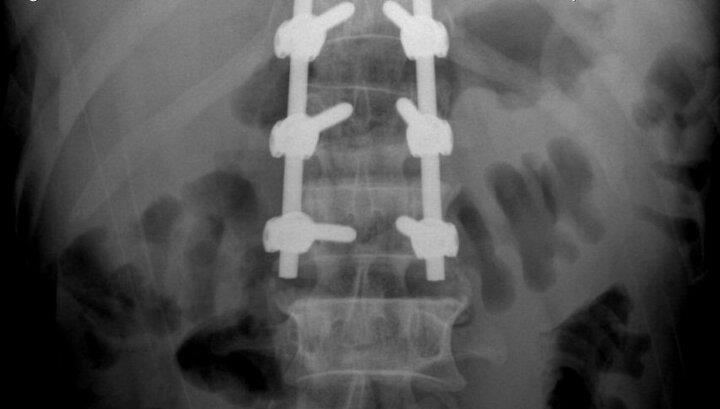

Người đàn ông 51 tuổi (ở Tuyên Quang) phải phẫu thuật cố định đốt sống do ngã xuống từ độ cao 3m dẫn đến vỡ đốt sống thắt lưng, mất vững, thoái hóa đa tầng các đĩa đệm và đốt sống thắt lưng.